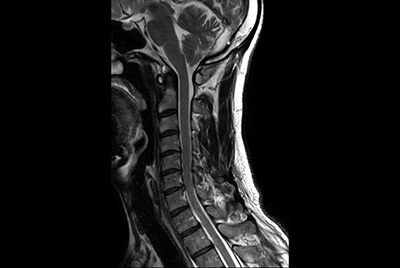

Neck stenosis

Cervical spine imaging with robust fatsat

Shorten exam time with Compressed SENSE in cervical spine

Cervical Spine - Cord lesion

Cervical Spine with mDIXON XD

Cervical Spine with acoustic noise reduction

Cervical Spine imaging with mDIXON TSE

Comprehensive Cervical Spine imaging at 3.0T

Comprehensive Cervical Spine imaging at 1.5T